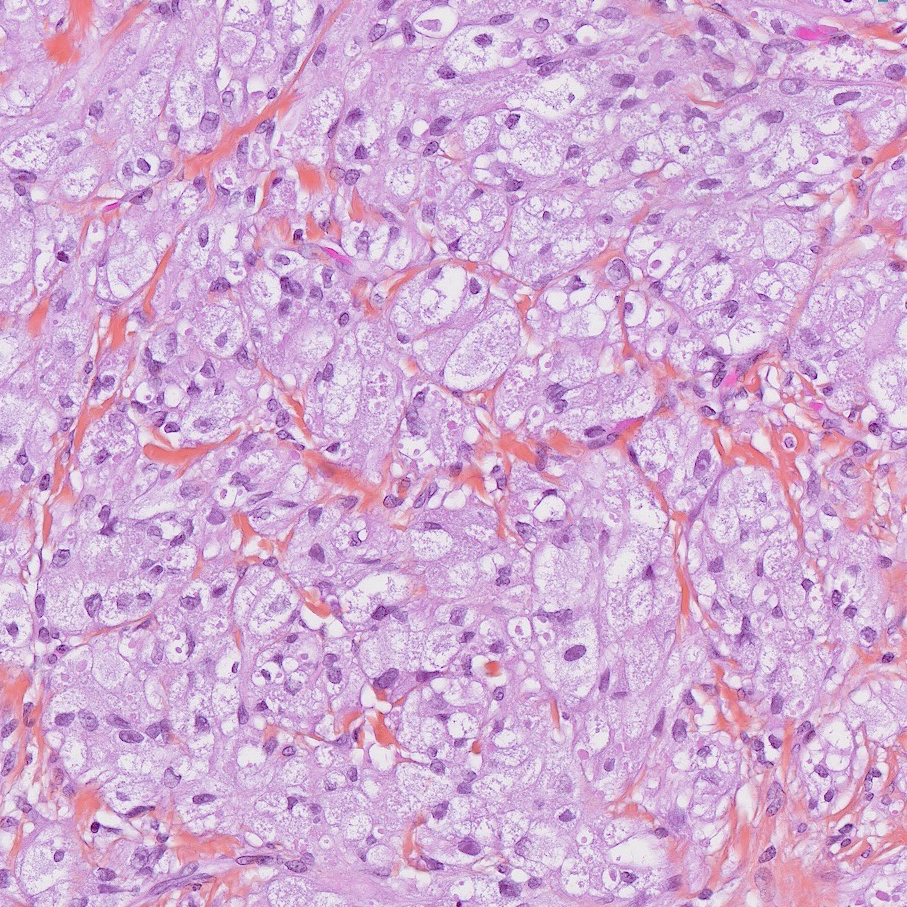

Le diagnostic formel repose sur l’histologie : cellules polygonales à cytoplasme granuleux éosinophile, à coloration PAS (Periodic Acid Schiff) positive (fig. 2). L’immuno-histochimie est caractéristique.